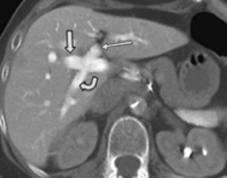

Fig. 1 - Anatomia standard a venei porte

Barbat de 45 de ani cu cancer colorectal metastatic.

CT indica anatomia standard a venei porte.

Vena porta principala se divide în vena porta stânga si cea dreapta, care se divide în vena porta dreapta anterioara (care iriga segmentele V si VIII) si vena porta dreapta posterioara, care iriga segmentele VI si VII.